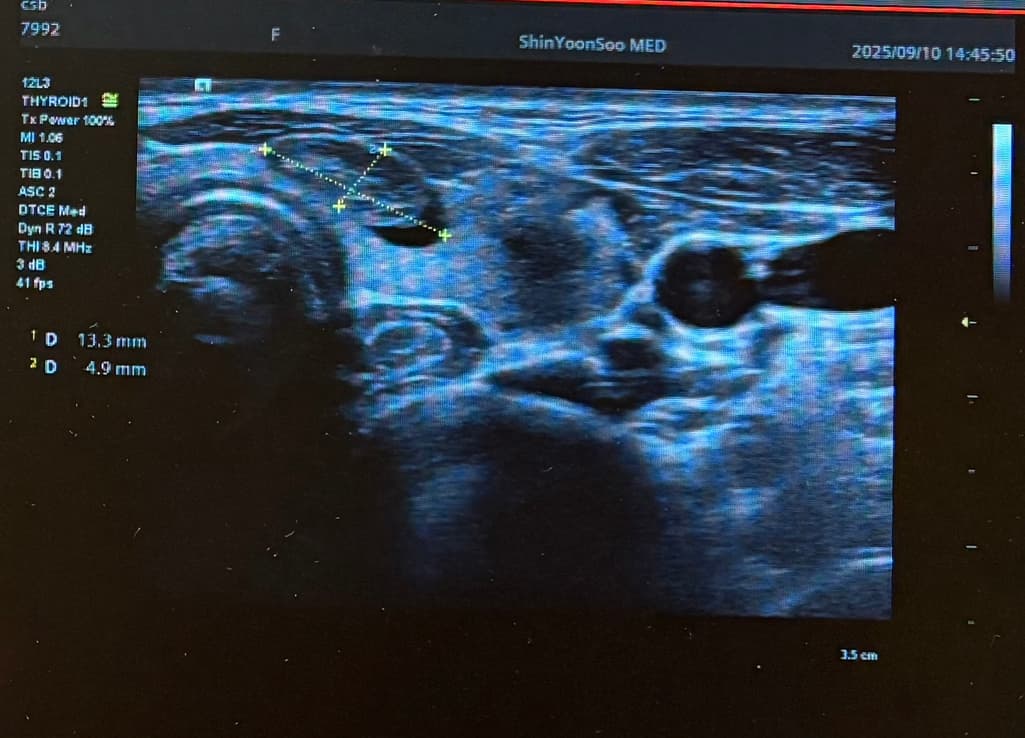

Lt 1ower lobe

1.88x1.4x2.84cm mixed nodule Lt middle lobe 1.22x0.37x 0. 49cm의 nodule 소견으로(의뢰서에 적혀있던 내용) 초진 보러가니 초음파 사진만 보시고는 식도와 신경에 들러붙어있고 점점점 커지면서 추후엔 응급수술로 진행될 수 있으니 아직 젊을때 빠르게 수술로 떼어내자고 결론은 수술밖에 없다고 냅다 수술일정 한달뒤로 잡고왔습니다.

왼쪽에 약 3cm가량으로 전체가 혹일거라며 상황이 많이 안좋은거고 위치가 안좋다고 하셔서 다음주에 수술전 검사 받은 후 2주뒤 입원으로 일정이 잡혔는데 보통 세침검사 또는 총생검사 후 수술 여부가 결정되는걸로 알고있는데 ..